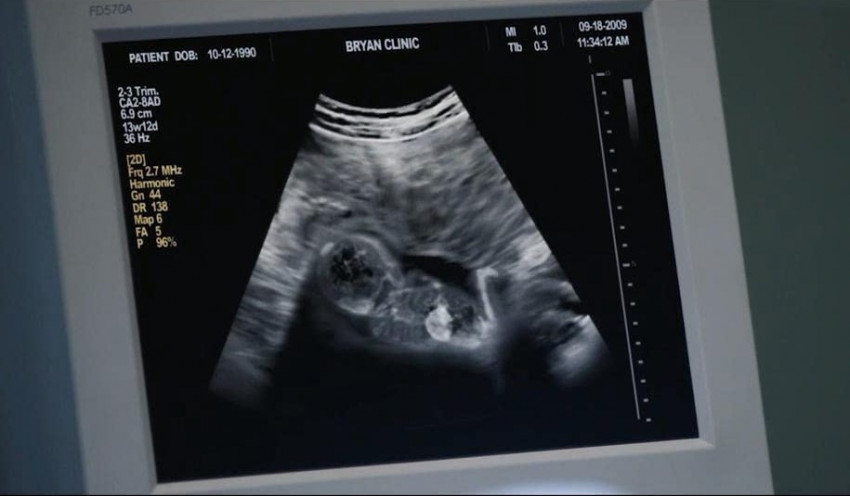

Ám egy nap, teljesen váratlanul segédkeznie kell a műtőben az abortusz elvégzésénél, és akkor látja az ultrahangos képernyőn, amint a tizenhárom hetes magzat kétségbeesetten küzd az életéért, menekülni próbál, majd eltűnik. Ez az a pont, amikor Abby rádöbben, hogy miben vett részt tevékenyen, csaknem tíz esztendeig. Azonnal felmond és jelentkezik a 40 Nap az Életért mozgalomnál, ahol szeretettel fogadják, nem ítélkeznek fölötte. Abby ekkor szembesül tetteinek a valódi súlyával, bűntudat gyötri: megbocsátja-e neki Isten, hogy aktívan segédkezett több mint 22 ezer magzat elpusztításában? Hogyan lesz képes ennek a terhével élni? A férje, Doug az, aki vigasztalja: ha belátod, hogy bűnt követtél el, megbánod és bocsánatot kérsz, Isten megbocsát neked, mert Ő Isten, és szeret téged.